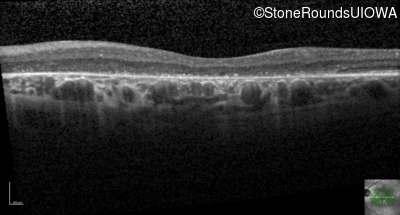

Cone-Rod Dystrophy (IA1b)

Age at visit: 58 years

This 58 year old woman first noticed a gap in the vision of her left eye at age 46.

Diagnosis & molecular findings

Disease Gene Allele 1 variant(s) Allele 2 variant(s) Inheritance mode

Cone-Rod Dystrophy CRB1 Cys948Tyr (T)GT>(T)AT Asp165 del9cagGATGGAATT AR